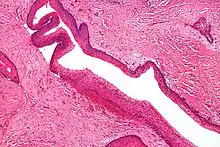

داء السلائل الورمي الغدي العائلي

داء السلائل الورمي الغدي العائلي (FAP) هي متلازمة صبغية جسدية سائدة تزيد من خطر الإصابة بسرطان القولون والمستقيم. وتصيب تقريبًا شخص من بين كل ثماية الآلاف شخص ولديها انتفاذ بمقدار 100%. تغطي مئات الآلاف من الأورام الغدية الحميدة قولون الشخص المصاب بالكامل، وتؤدي في معظم الحالات إلى الإصابة بالسرطان. وتشمل الأمراض التي تزيد بشكل متكرر التالي: الأورام العظمية، وأورام الغدة الكظرية والأورام السرطانية وأورام الغدة الدرقية، والأورام الرباطية. يحدث هذا الاضطراب بسبب تحور جين (APC) الذي ينظم بروتين (β-catenin). يسبب خلل جين (APC) تراكم بروتين (β-catenin) في الخلايا وتنشيط عوامل الاستنساخ التي تتضمن تكاثر الخلايا، ونزوحها، وتمايزها، وموت الخلايا المبرمج.